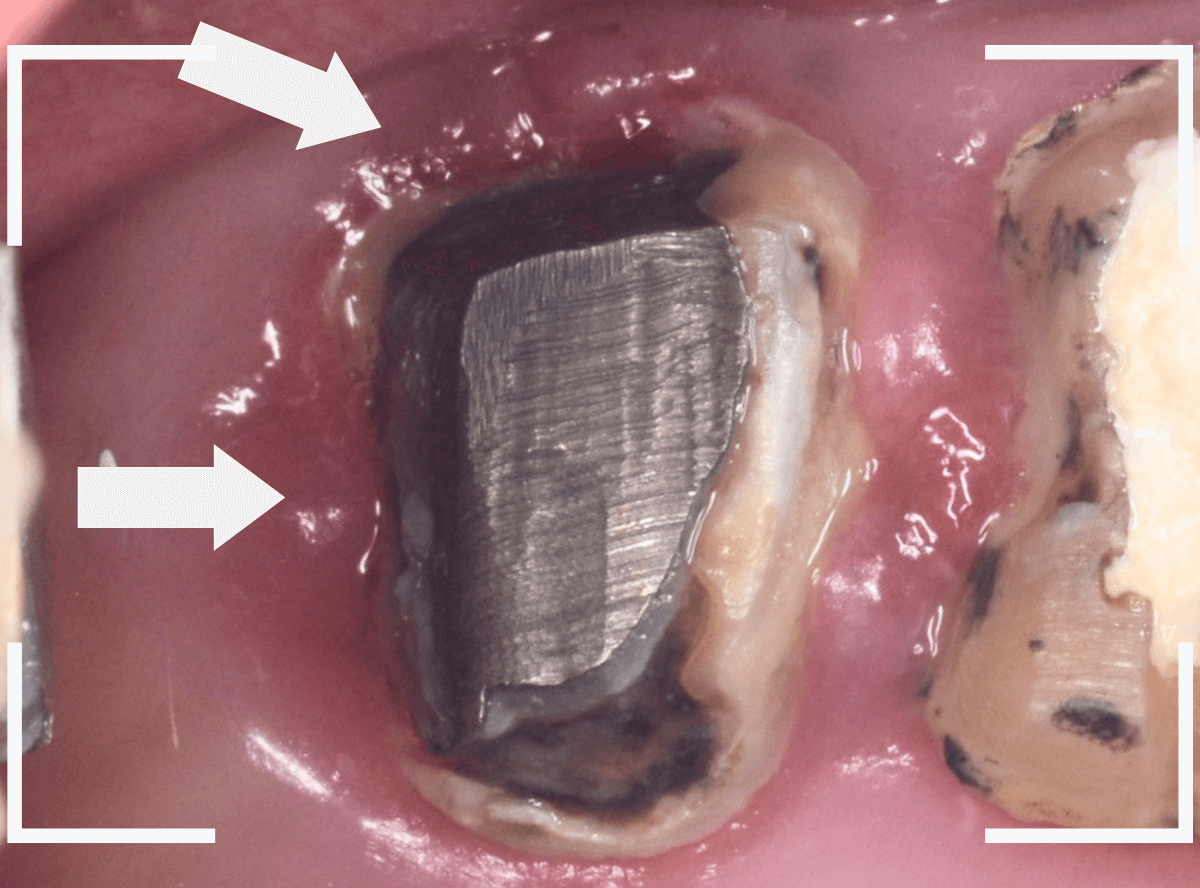

Case.1

こちらは比較的簡単な歯の土台の再治療のケースです。

下の奥歯の虫歯の治療後に、金属の土台(メタル・コア)をsetして、長期間放置してしまいました。

見た目的にはあまり問題なさそうにみえましたが、奥歯との間の歯肉が若干炎症気味でぶよぶよしてるのが気になりました。

レントゲン写真で確認すると、歯の奥側が虫歯になり始めています。

虫歯のすき間に物がつまりやすくなり、歯肉の状態がイマイチだったのかもしれません。

この虫歯を除去しないままさし歯をお作りしても、よい治療にはなりません。

短期間で外れて再治療になる可能性も高いですので、まずは虫歯の再治療をします。

メタル・コアを除去して、明視野で虫歯を確認します。

幸い、浅い状態に入っていたメタル・コアでしたので比較的容易に除去する事ができました。